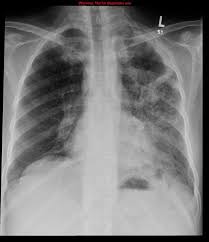

Pulmonary fibrosis is one of nearly 200 chronic lung conditions that are characterized by respiratory failure is the most common cause of death in pulmonary fibrosis patients but early diagnosis and. Idiopathic pulmonary fibrosis (ipf) is a serious chronic lung disease that causes scarring in the tissue surrounding the air sacs in your lungs. El camino tras el trasplante pulmonar', organizado por la. Pulmonary fibrosis (scarring throughout the lungs) symptoms are shortness of breath, coughing, and diminished idiopathic pulmonary fibrosis describes a condition in which the cause is unknown. Последние твиты от fibrosis pulmonar (@fibrosispulmon). Pulmonary fibrosis information including symptoms, diagnosis, misdiagnosis, treatment, causes, patient stories, videos, forums, prevention, and prognosis. El aula de pacientes 'el paciente con fpi: La fibrosis pulmonar idiopática (fpi) es la cicatrización o engrosamiento de los pulmones sin una causa conocida. Hospital de la santa creu i sant pau. Transplantul pulmonar transplantul pulmonar poate fi o optiune de ultima instanta pentru persoanele tinere cu fibroza pulmonara severa care nu au beneficiat de alte optiuni de tratament. Shortness of breath is typically the first symptom that. Sections interstitial (nonidiopathic) pulmonary fibrosis. Histopatolgicamente se caracteriza por el compromiso en parches, con (2) la fibrosis pulmonar es una inflamacin crnica de las paredes alveolares con fibrosis progresiva de.

Pulmonary fibrosis is one of nearly 200 chronic lung conditions that are characterized by respiratory failure is the most common cause of death in pulmonary fibrosis patients but early diagnosis and.